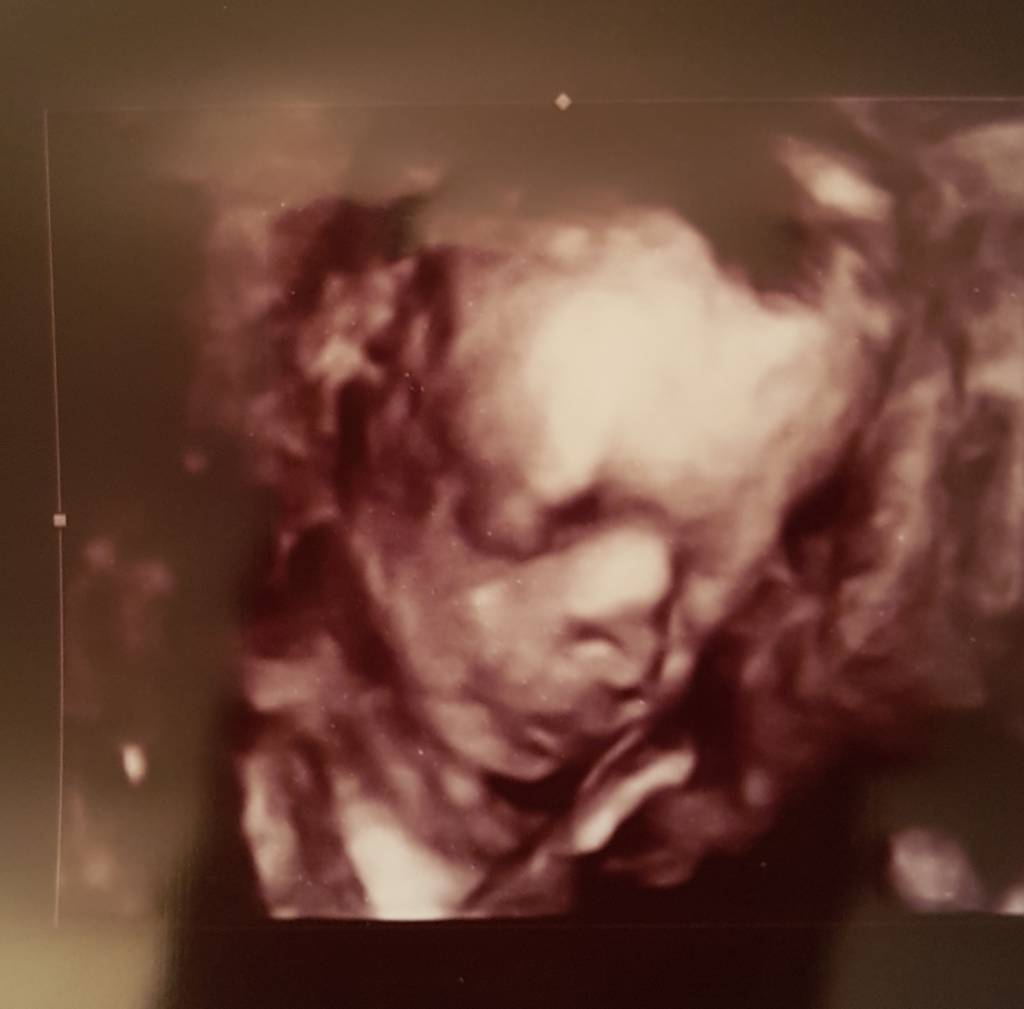

A to moja Kalinka.